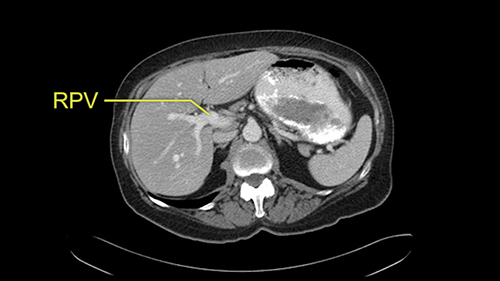

The procedure-specific slowing down moments from a technical point of view for a right hemihepatectomy include a careful evaluation of the inflow structures including the right hepatic artery, the right portal vein, as well to make sure that I have identified and preserved the left hepatic artery and the left portal vein at all times, and minimize any injury or dissection of the common bile duct. Also, I am careful when I mobilize the right liver, not to tear the right triangular ligament and cause bleeding of the liver as I mobilize it off the retroperitoneum and the bare area. In addition, the last procedure-specific slowing down moment is to carefully identify the right hepatic vein and ensure that I encircle it safely without damaging the IVC or the middle and left hepatic vein structures at all times.

In addition, as I plan this operation, I will also look at the size of the small tumors. They’re very small, some are less than one centimetre in size, and carefully evaluate the relationship between the small tumors and the surrounding vascular structures. If I cannot see or feel the tumors at the time of surgery, I will use the blood vessels in order to landmark and plan my operation.

![[RHA]](jpg/preop_sg_moment3.jpg)

The only other most important feature that I usually consider is the portal vein split or the bifurcation, especially if doing a major liver resection like a right lobe. I like to look at the length of the common right portal vein trunk which looks like its probably long enough to put a stapler on. Final decision would be in the OR. If it wasn’t long enough and I was concerned about injuring the bifurcation or the left portal vein, then I would divide the Segment 5-8 and 6-7 portal tracks individually.

![[LPV]](jpg/preop_sg_moment4b.jpg)

This patient has an interesting minor anomaly with what looks like a Segment 7 portal vein coming off close to the bifurcation of the right portal vein but again if I was doing a right lobe which is my plan, this wouldn’t be an issue.